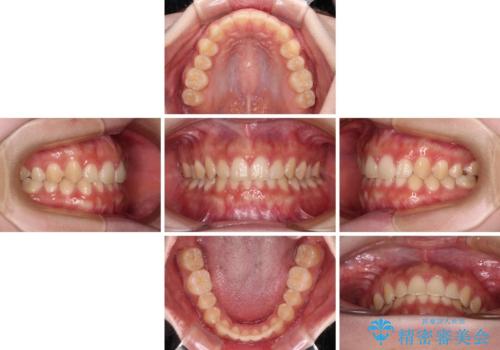

- 上顎前歯の隙間を気にして来院された患者様です。

目立たない装置を希望とのことで、インビザラインを用いて矯正治療を行うこととしました。

一度インビザラインのマウスピースセットをお渡しすると1年以上来院されず、マウスピースを破損したり紛失したりすると来院されるというのんびりとしたペースで治療を行ったため、4年間という長期にわたる治療となりました。

最終的には隙間は全て閉じ、綺麗な仕上がりとなりました。